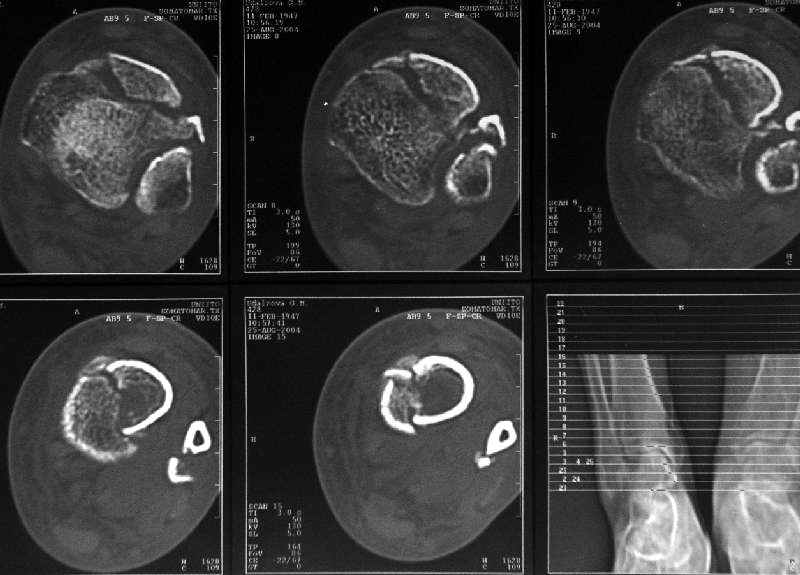

Сейчас вот, получается, спохватились. Снимки и КТ в приложении. Какой вариант тут предпочтительнее - открытая мобилизация, репозиция и внутренняя или наружная фиксация? Или ограничиться только резекцией костного шипа над шейкой тарана?Заранее спасибо.A female 56 y.o. 6 weeks ago sustained a fracture of the distal tibia/fibula. At the initial hospital a plaster cast was applied. Now she was referred to our unit. At the moment there is no pain, no obvious mobility. Images and CT attached.What is the best option here? Mobilize the fracture, perform open reduction and internal or external fixation? Or just to cut the anterior spike over the talar neck? THX in advance.

Однако именно по КТ как раз сложнее всего оценить состояние консолидации.

В этой связи БОЛЬШОЙ ВОПРОС:

Какова роль КТ при переломах диафиза длиннных костей:

- оценка положения отломков

- оценка сращения и пр.

В подавляющем большинстве случаев мне это исследование кажется неинформативным (я имею в виду исключительно диафизарные переломы).

В нашей, например, практике - никакая. То есть для диафизарных переломов - не пользуемся, т.к. необходимости не испытываем. Суставы, таз - другое дело.

Оно избыточно. Обычная рентгенография дает все, что надо, для оценки диафизарного перелома.

Здесь повреждение не диафизарное, смотрели состояние суставного конца кости и взаимоотношения таранной кости с этим шипом. Результаты КТ как раз повлияли на план, без нее пошли бы латеральным доступом, а после - передне-медиальным.

Для диагностики внутрисуставных и вколоченных переломов томография информативна и практична, а если есть возможность трехмерной реконструкции, то это и наглядно представляет характер перелома.